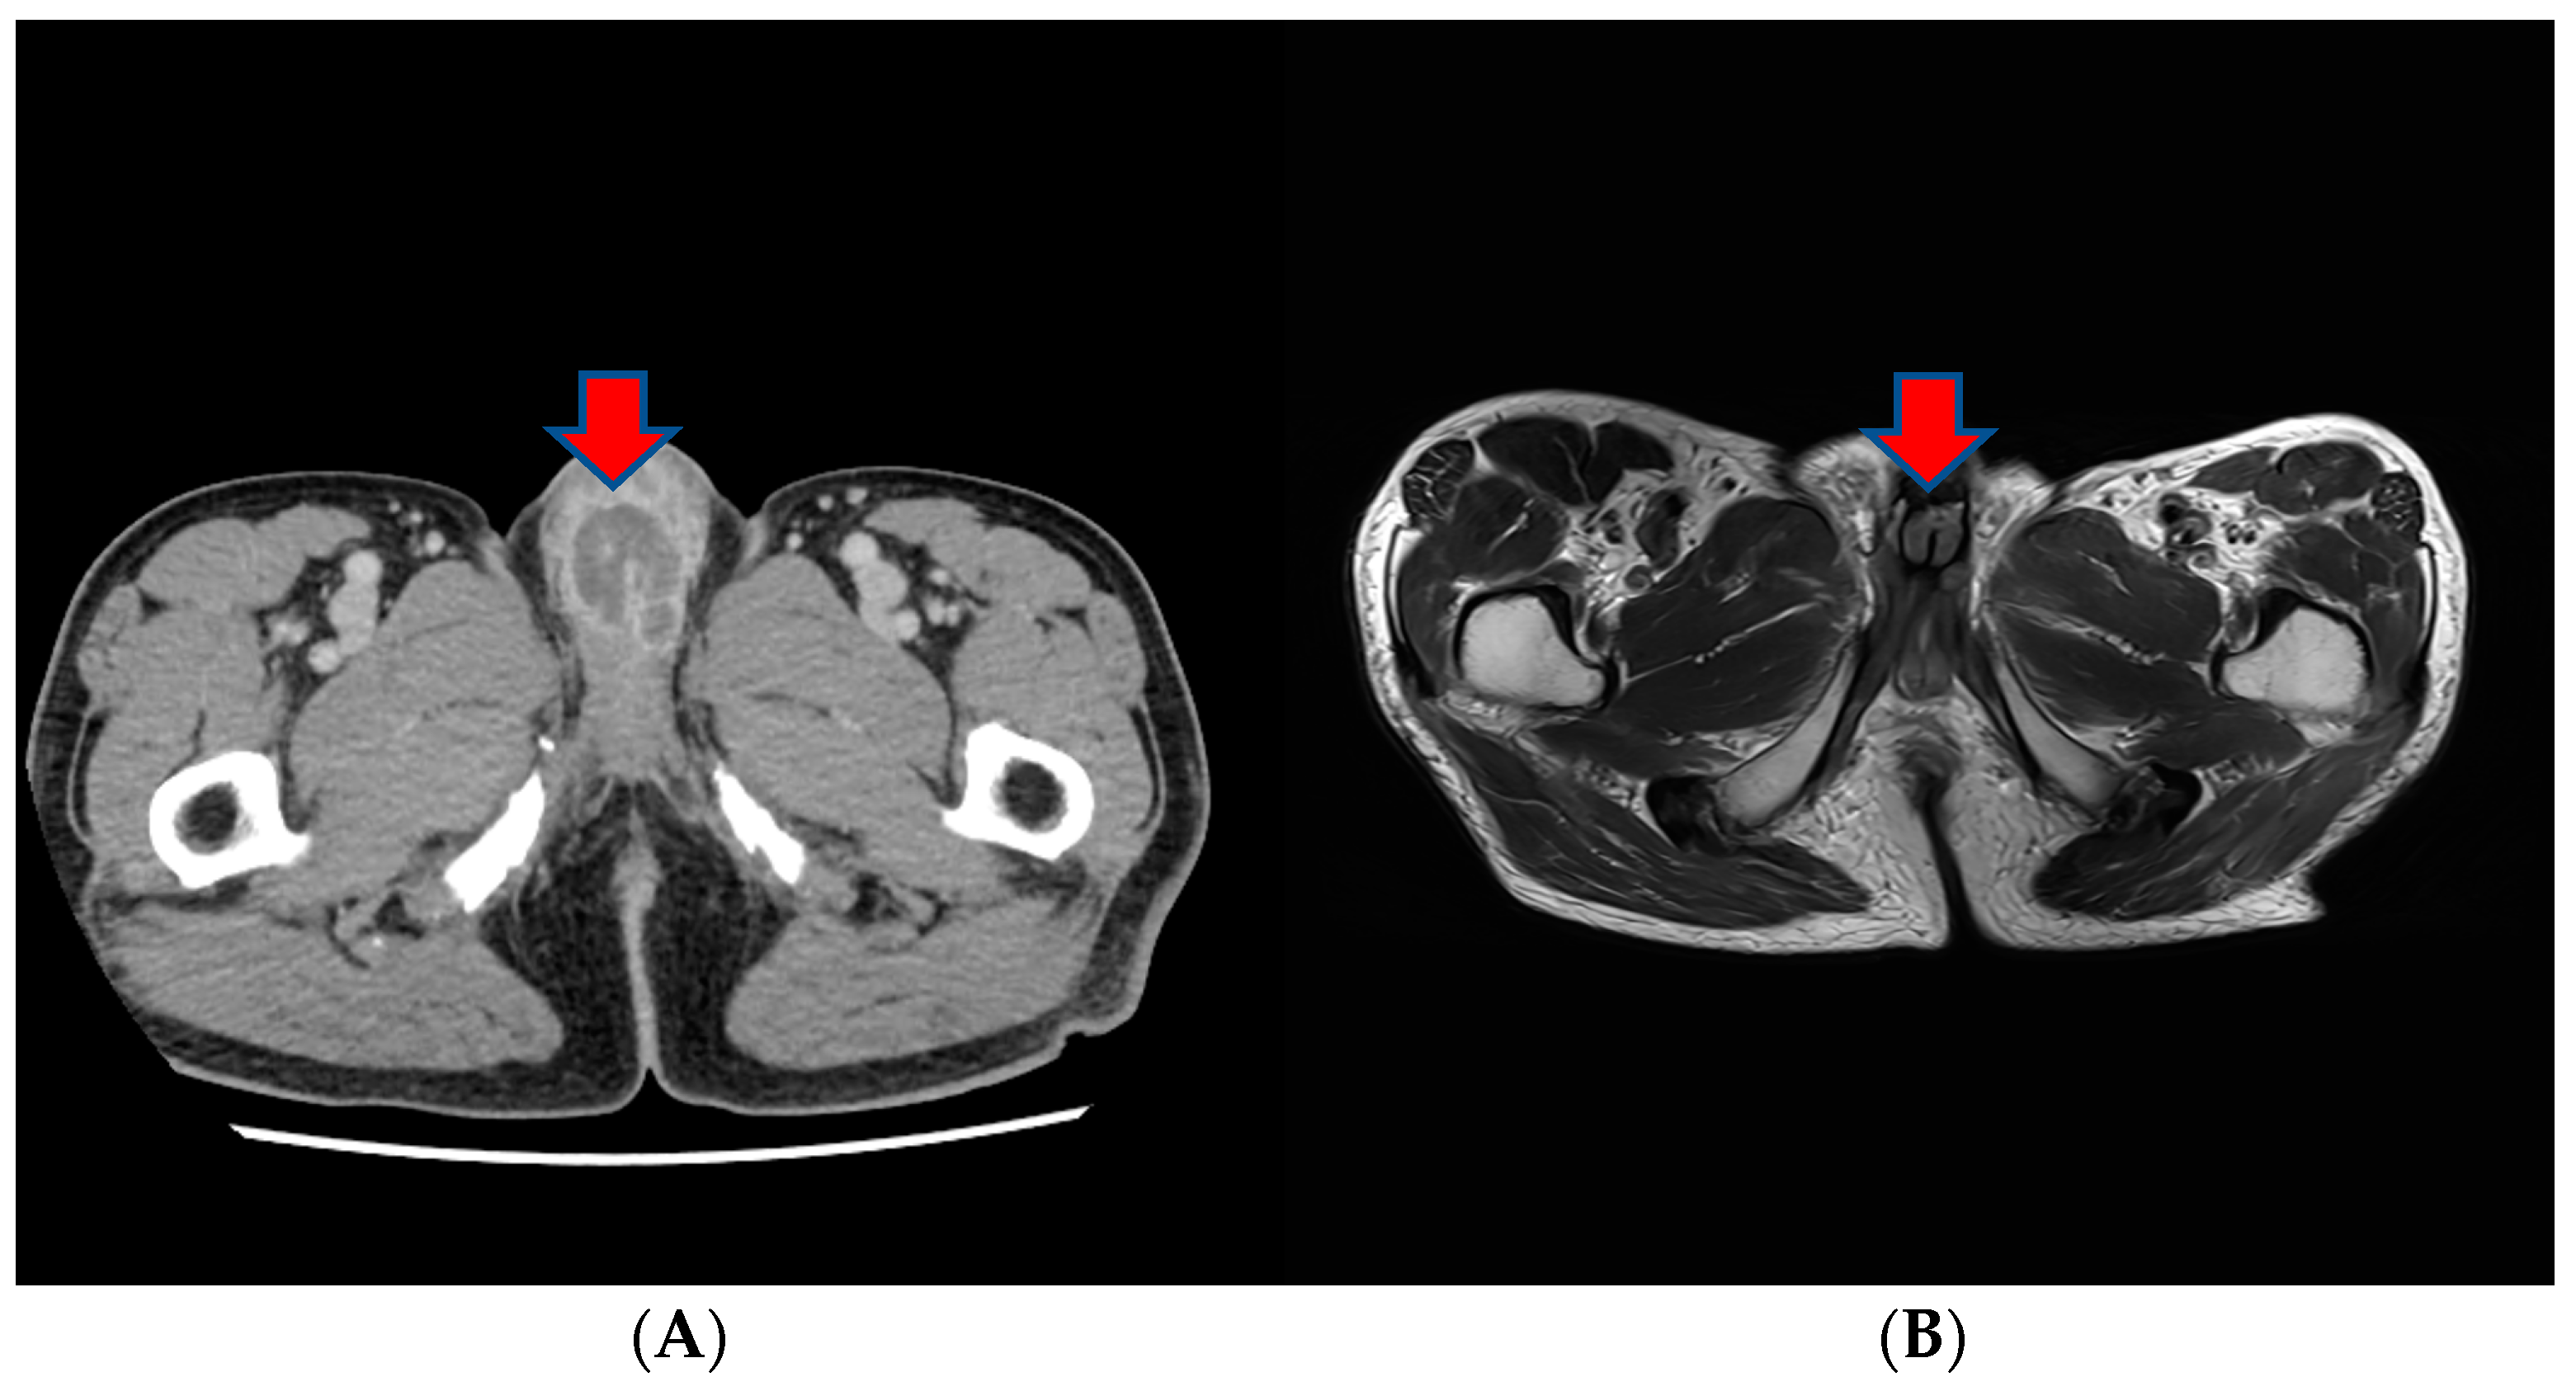

However, in a subsequent CT scan performed approximately 4 months later, an increased size of the mass in the penis was observed, and persistent penile pain led to the consideration of radiation therapy (Figure 4). After radiation therapy, a follow-up CT scan showed a decreased tumor size (5.1 cm to 3.4 cm) (Figure 4).

Figure 4.

(A) A subsequent CT scan performed approximately 4 months later showing an increased size of the mass in the penis. (B) After radiation therapy, a follow-up CT scan showed the decreased size of the tumor.